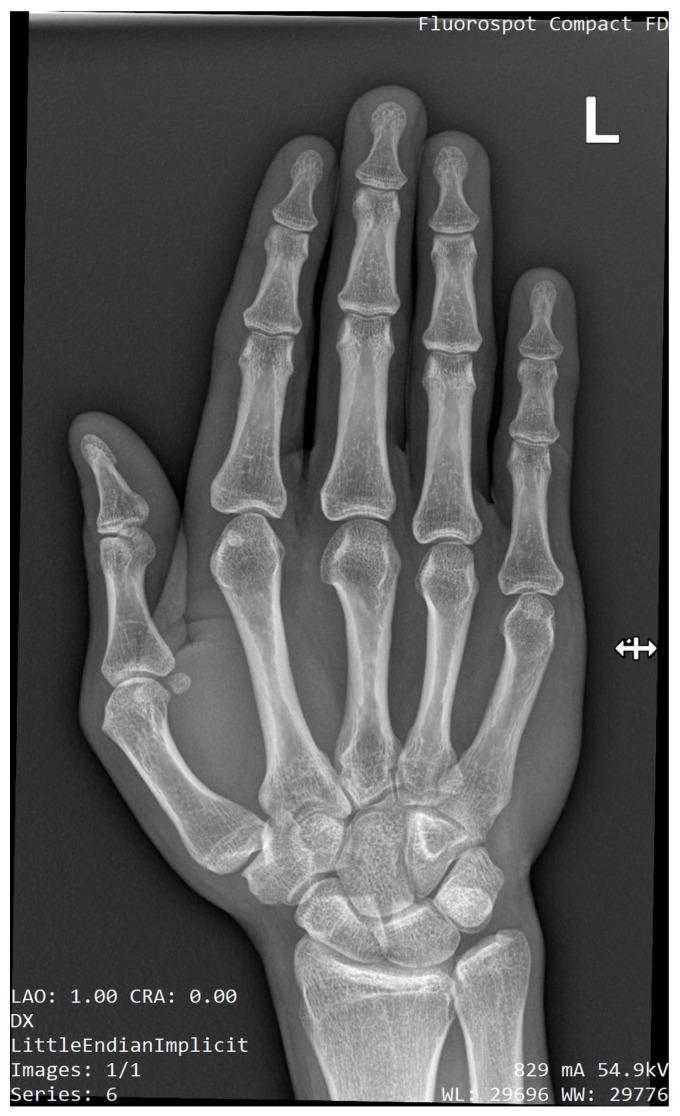

近侧桡尺骨融合(PRUS)是最常见的先天性前臂疾病,尽管其在普通人群中的患病率较低,仅有数百例报道。Pfeiffer、Poland、Holt-Oram 和其他严重的先天性综合征都包含这种异常。非综合征性病例中,孤立的 PRUS 常与 SMAD6、NOG 基因变异或性染色体非整倍体有关。一小部分伴有血液学异常的患者表现为 HOXA11 或 MECOM 基因变异。我们报告了一名非综合征性成年冰球精英运动员,其左侧前臂存在单侧近侧桡尺骨融合。在幼儿时期,他只能像右撇子一样使用曲棍球棒,并且由于缺乏旋后,直到 8 岁才确诊。X 光片显示为 Cleary-Omer Ⅲ型 PRUS,伴有桡骨头发育不良和肱尺关节轻度骨赘退行性变。由于该病症对体育活动的影响极小,因此未考虑手术干预。该运动员继续在顶级水平上从事冰球运动,并加入了国家队参加顶级比赛。问卷调查和体格检查上肢功能评估结果显示,损伤极小。受影响最大的工具是 Failla 评分,总分为 15 分,得分为 10 分。Sanger 测序的基因检测未发现 和 基因中有意义的致病性变异。通过基于阵列的比较基因组杂交未检测到潜在致病性拷贝数变异。在报告的病例中,运动员有能力应对限制前臂旋后功能的解剖变异。如今,通过不断发展的遗传学,可以全面排除更复杂的肌肉骨骼损伤和家族负担。